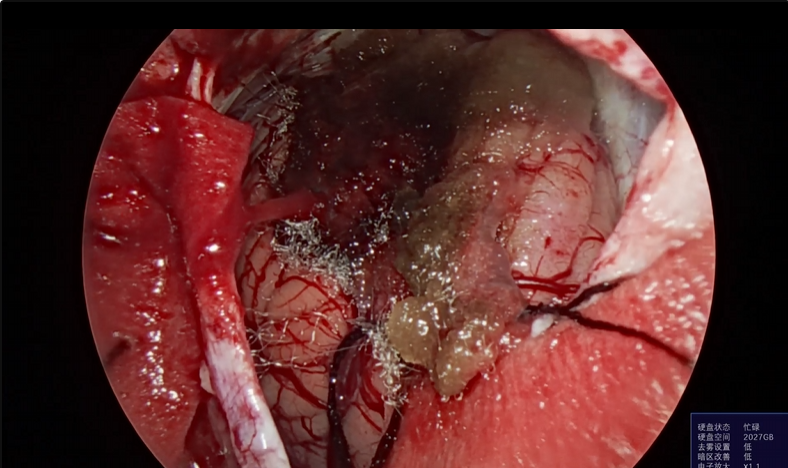

神经外科垂体瘤手术